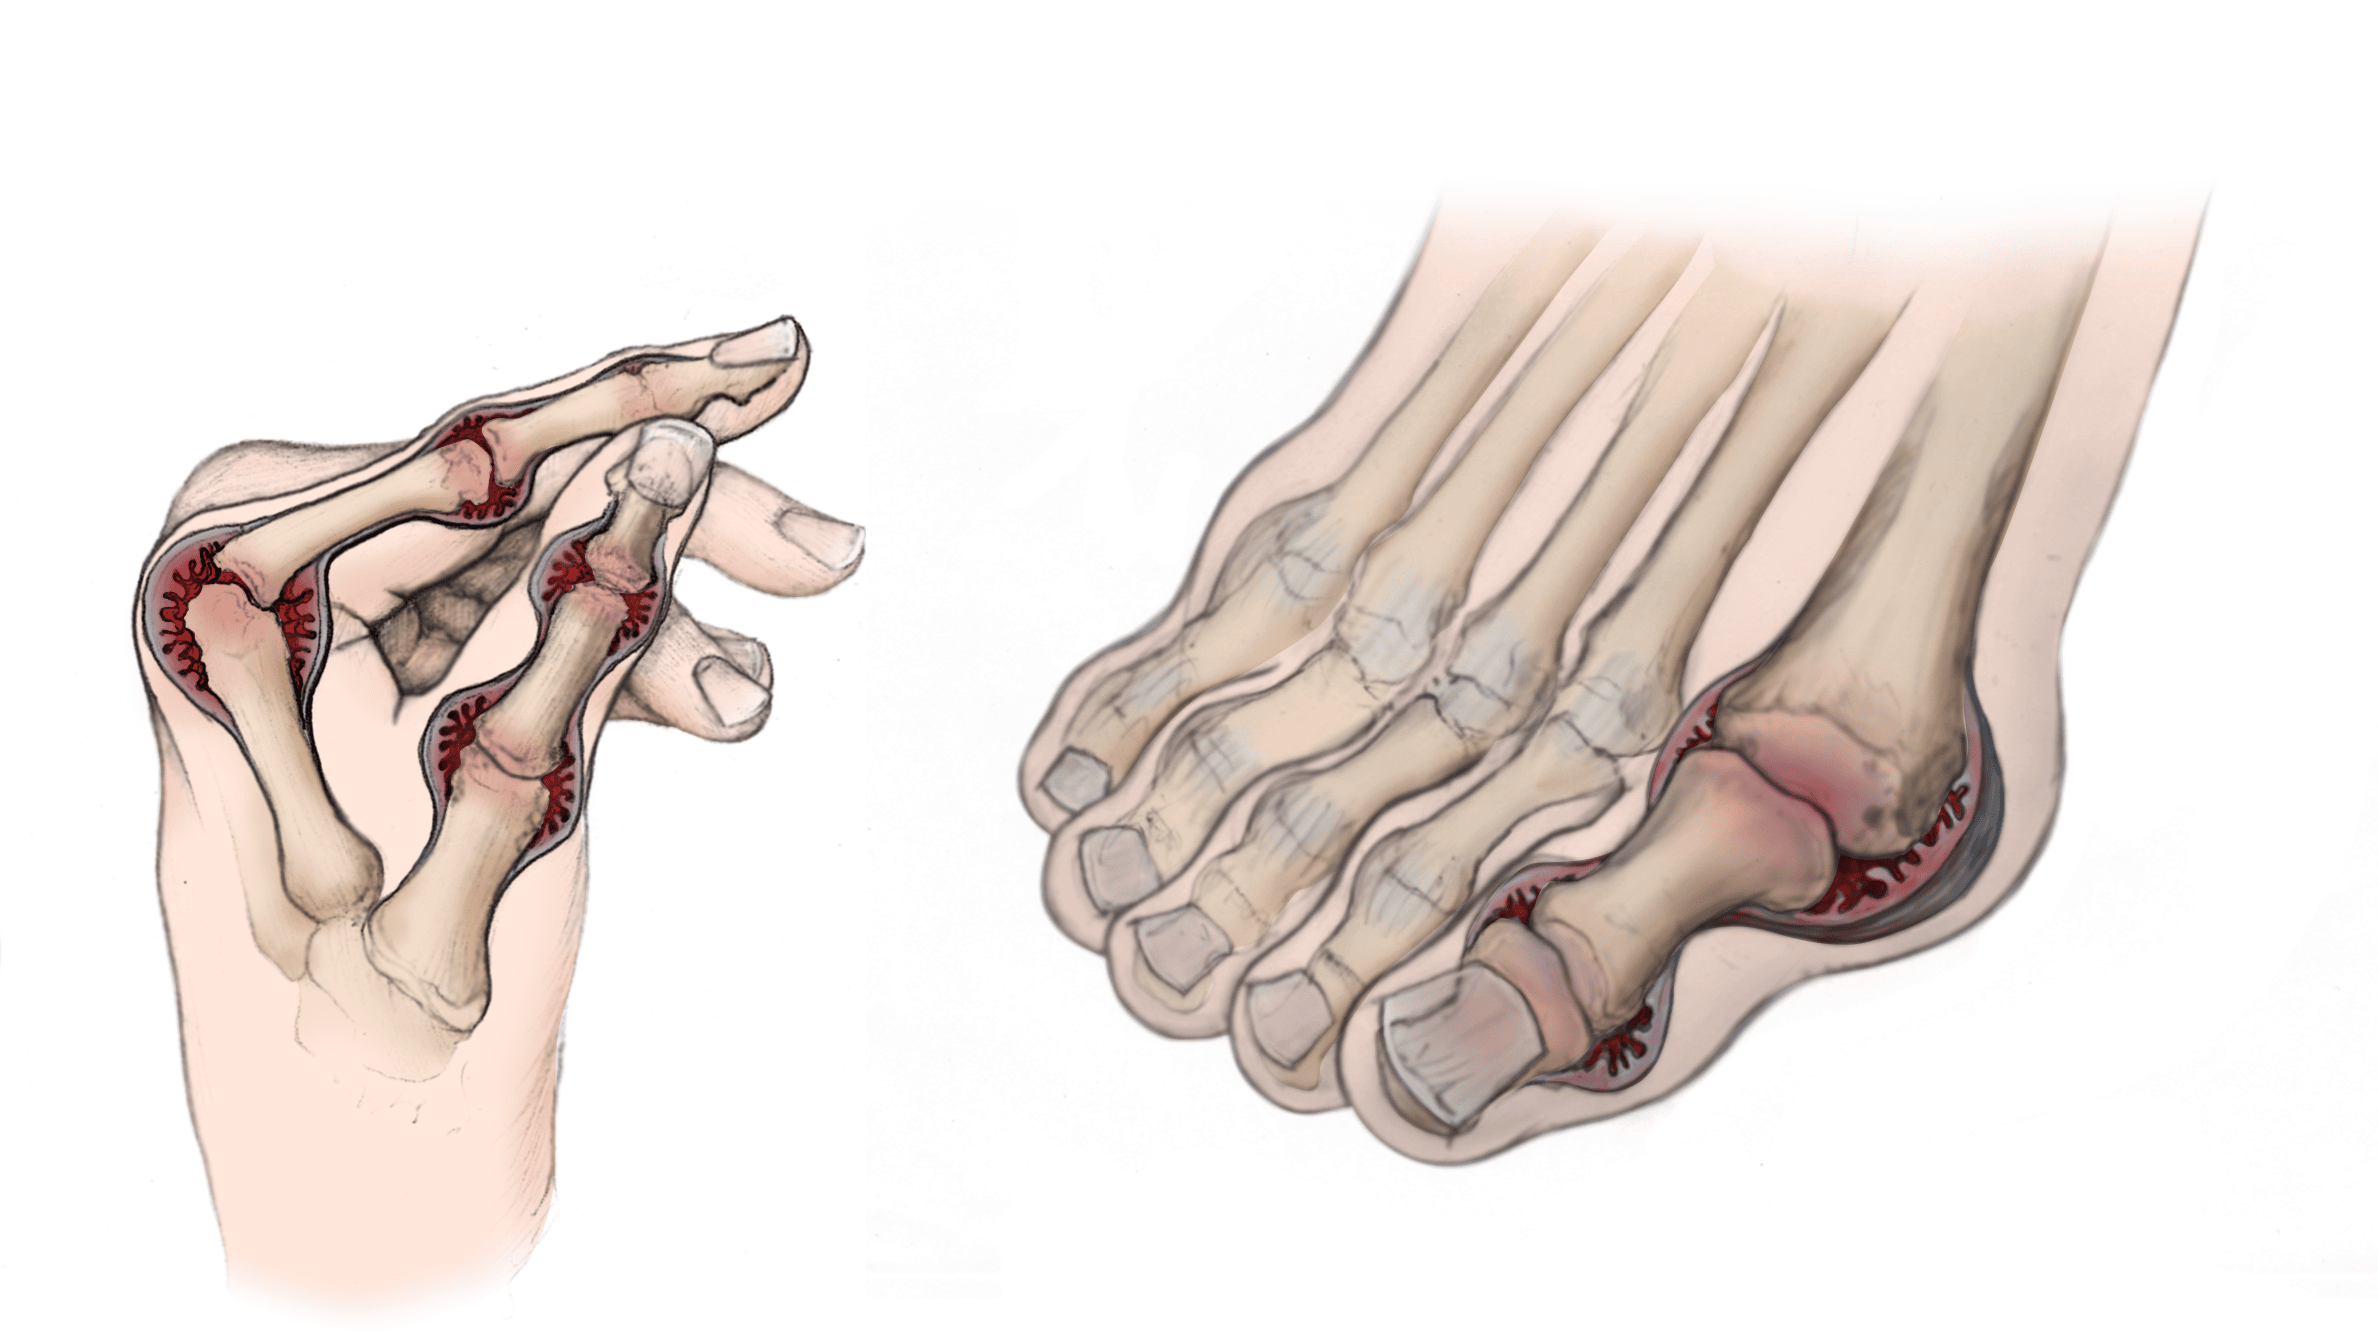

Rheumatoid Arthritis in the Hand and Foot

The small joints in the hands and feet are often the first to be affected by rheumatoid arthritis.

Reproduced from The Body Almanac©. American Academy of Orthopaedic Surgeons, 2003.